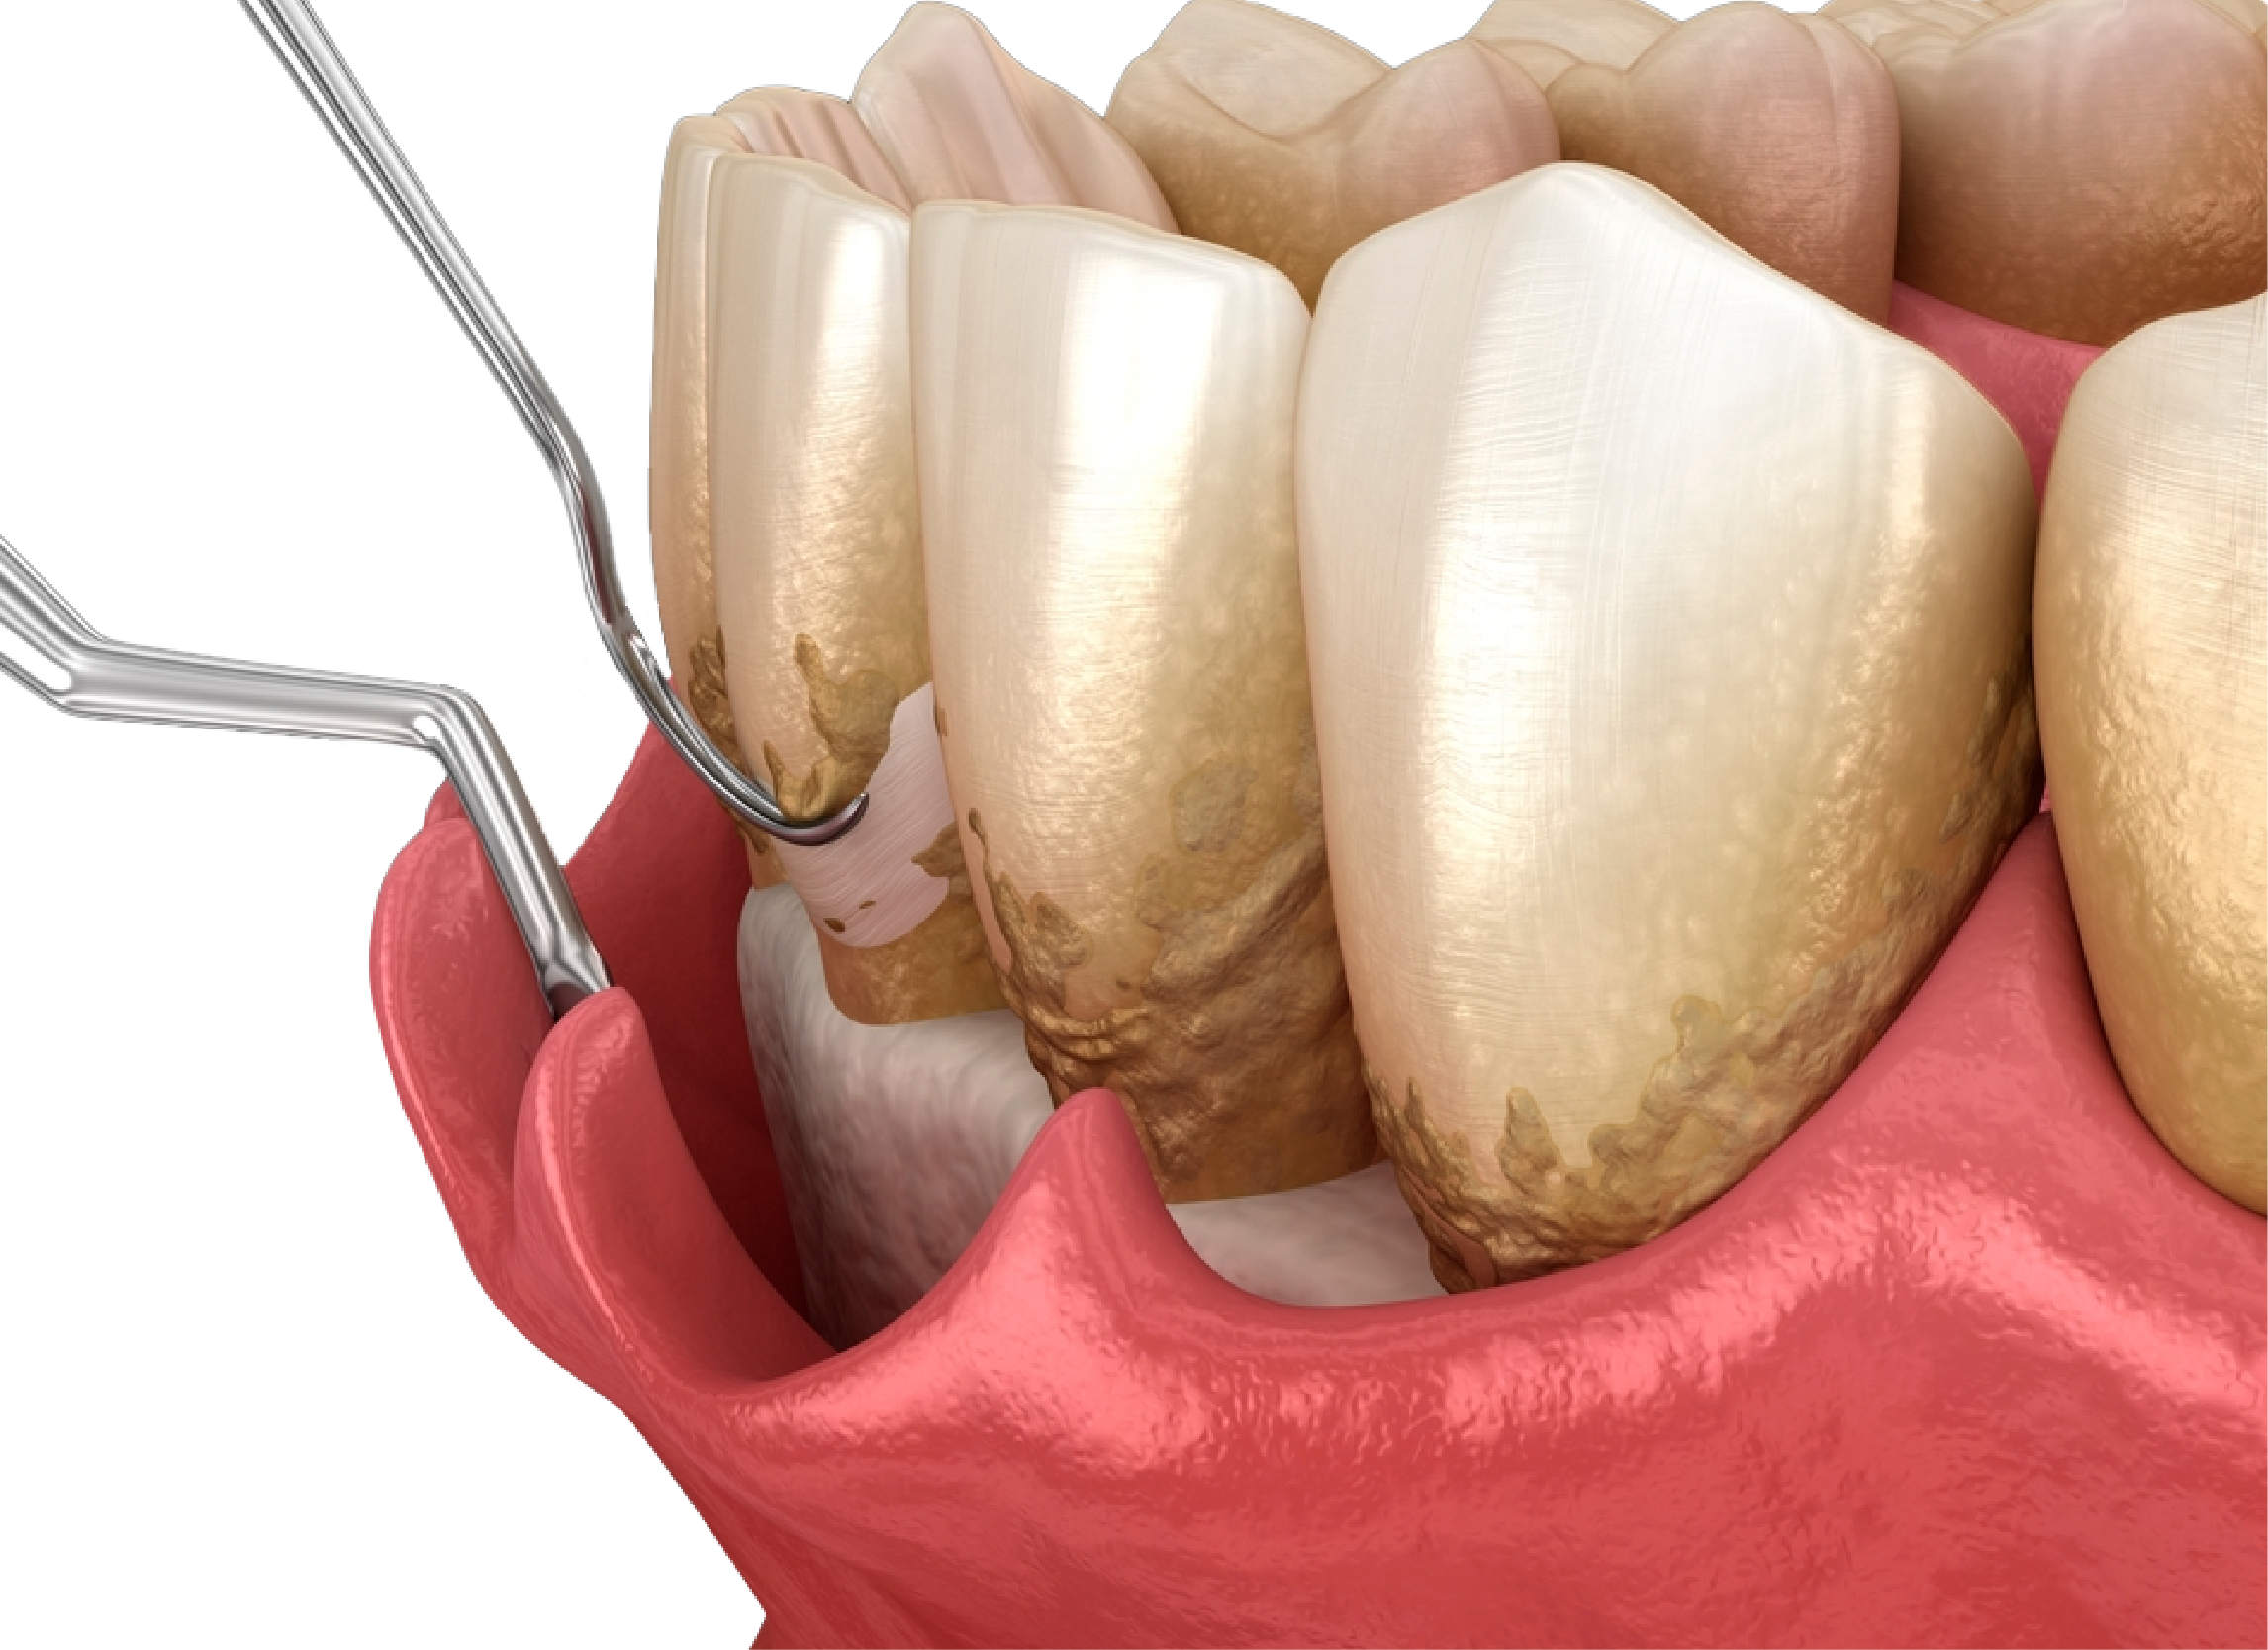

Periodontitis

La Periodontitis es una infección grave de las encías que daña el tejido blando y destruye hueso que sostiene los dientes.